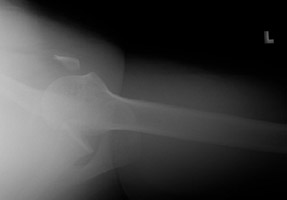

- Click on the image for a larger versionBAxillary radiograph of the left shoulder. This demonstrates the anterior dislocation as well as better depicts the coracoid fracture.